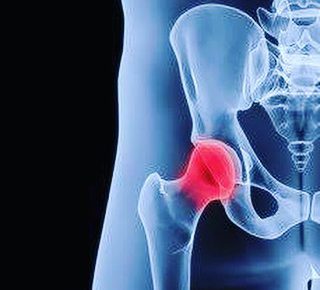

こんばんは!横浜本牧パーソナルトレーナー宮原崇です。 先日、ご紹介で股関節のお悩みを抱えている方からご相談を受けました。 フィットネスクラブでも非常に多くの方がお悩みを抱えていて、それに対しての対処法はプールで歩くという…

こんばんわ!横浜本牧パーソナルトレーナー宮原崇です。 昨日から仕事の合間に、とある競技の試合に出るために特訓をしているので、更新が夜になってしまいました。 さて、昨日は股関節を痛めたり、膝の抱え込みの姿勢の時に詰まり感が…

こんばんわ!横浜本牧パーソナルトレーナー宮原崇です。 昨夜の雷はすごかったですね!恐怖のあまり予定の仕事を早めに切り上げて、帰宅いたしました(笑)。 さて、よく股関節の痛みについてご相談を受けます。 実際に私のクライアン…

おはようございます!横浜本牧パーソナルトレーナー宮原崇です。 今日は久しぶりの晴天で気持ちが良いです。 先日お身体のご相談いただいた内容で、股関節を曲げた時に痛みが出るという方がいました。 股関節の痛みといっても前側が詰…

こんにちは!横浜本牧パーソナルトレーナー宮原崇です。 我々が人類が四つ足動物から二足歩行になれたのも股関節が伸展してくれたおかげです。 股関節に問題を抱えている高齢者が多いのも現実だと思います。 私も人工関節のご献体を解…

こんにちは!横浜本牧パーソナルトレーナー宮原崇です。 早いもので昨日は鏡開きでしたね。 さて、股関節にお悩みの方も多いと思いますが、今回は「Butt Griper」という症状をご紹介いたします。 主に股関節の前側や太もも…